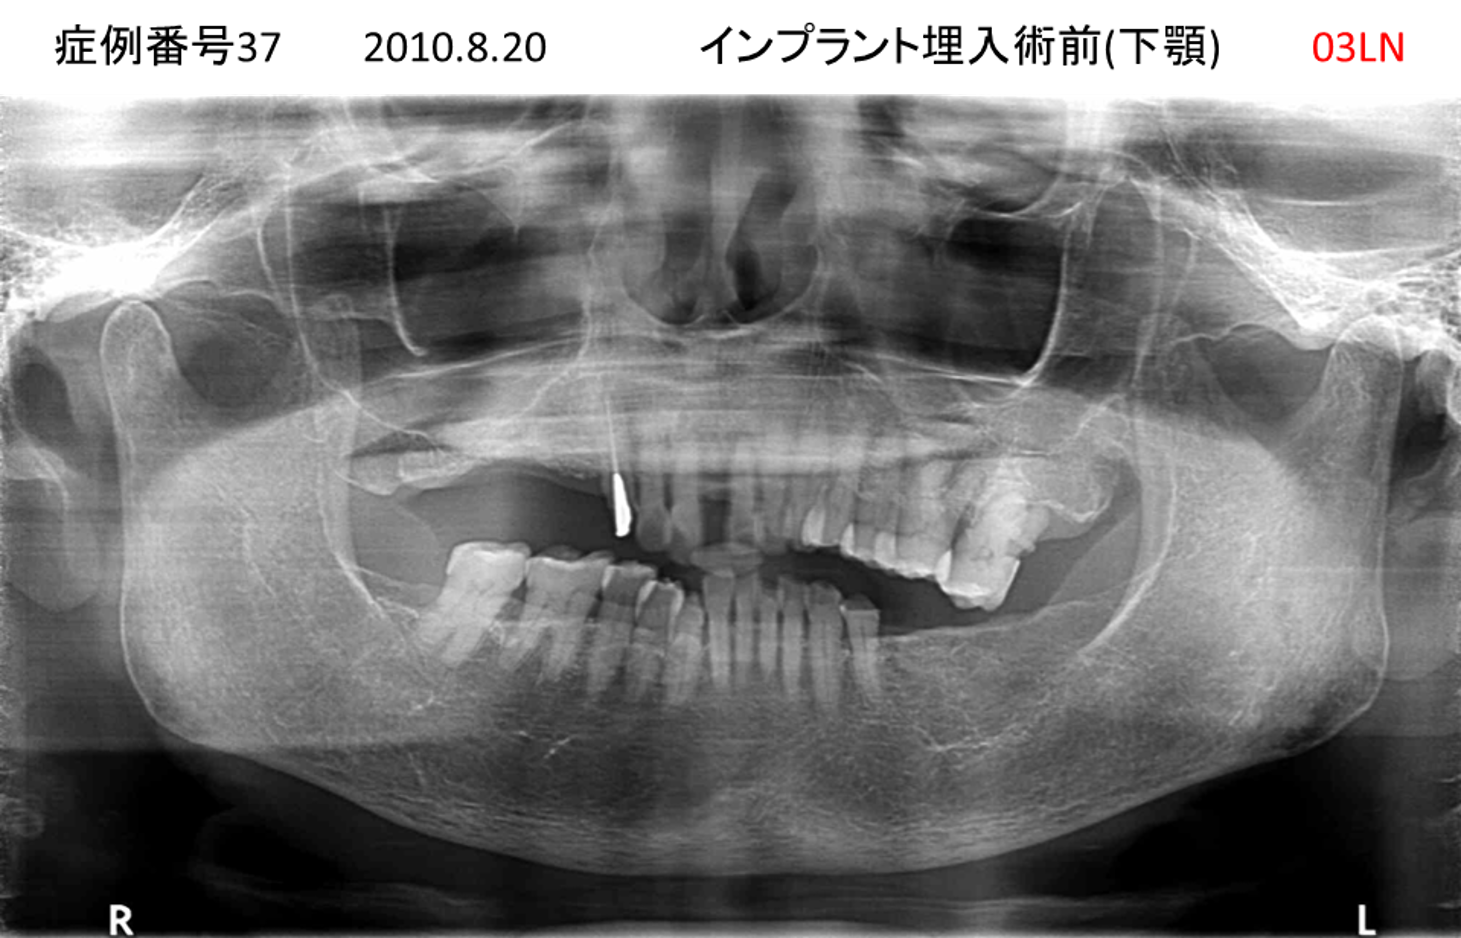

奥歯で噛めない患者様のインプラント症例

| 治療名称 |

インプラント |

| 治療費用 |

365万円+税 |

| 治療期間 |

5か月 |

| 患者さんの症状(主訴) |

奥歯で噛めない。上の前歯が揺れてきた。 |

| 治療内容 |

抜歯即時インプラント |

| 治療結果 |

食事に困らない。見た目がとても良くなった。 |

| 治療の注意点(リスク/副作用) |

インプラントが壊れたら再治療が必要 |